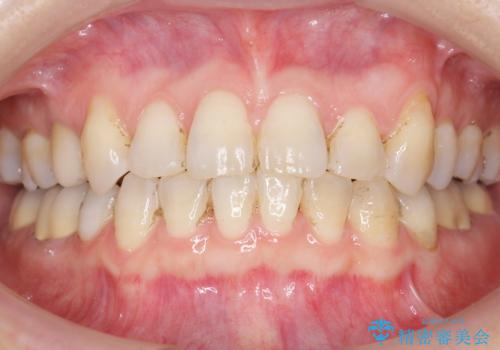

右上小臼歯(右上5)はオールセラミッククラウン(e-max press)、下顎臼歯(下顎両側67)はメタルボンドクラウンによりやりかえることにしました。

銀歯がなくなったとことで口元の印象が明るくなり、ご満足頂けました。

~クラウンの種類~

右上小臼歯(右上5):オールセラミッククラウン エコノミー

下顎両側臼歯(下顎両側67):メタルボンドクラウン エコノミー